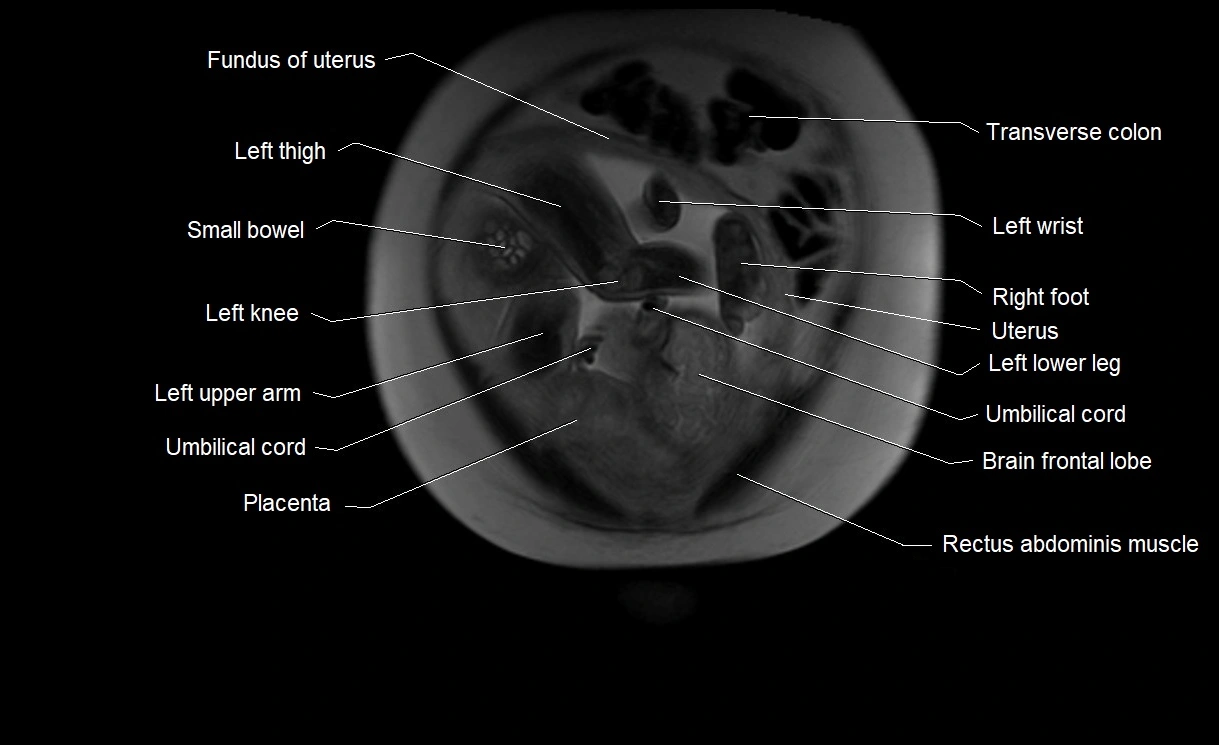

MRI Appearance

T2 HASTE (T2 GRE):

• Amniotic fluid shows very bright hyperintense signal

• Provides natural contrast against fetus and placenta

• Small particles (vernix) may appear as scattered hypointense foci within bright fluid